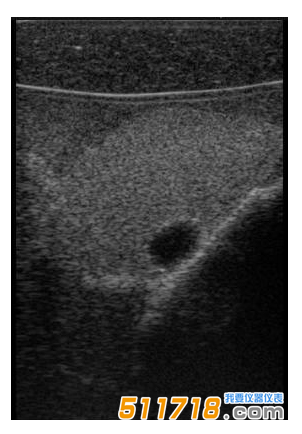

CIRS 074甲狀腺超聲訓(xùn)練模體包含一個略微擴大的甲狀腺,位于一個擬人化的頸部。下巴和鎖骨被提供作為外部解剖標(biāo)志。體模提供氣管,頸內(nèi)靜脈和頸總動脈作為內(nèi)部解剖標(biāo)志。每個甲狀腺葉包含一個囊腫和一個等回聲僵硬病變??梢栽诩谞钕賰?nèi)定制生產(chǎn)各種結(jié)節(jié)。*有材料都配制成超現(xiàn)實的。

略微擴大的甲狀腺包含單個囊腫和每個葉中的一個等回聲,僵硬的病變。

可以對每個囊腫進行細針抽吸。每個僵硬病變都設(shè)計用于超聲彈性成像的可視化,并且可以進行活組織檢查。這些病變對甲狀腺是等回聲的并且具有標(biāo)準(zhǔn)的B模式成像。

單純囊腫